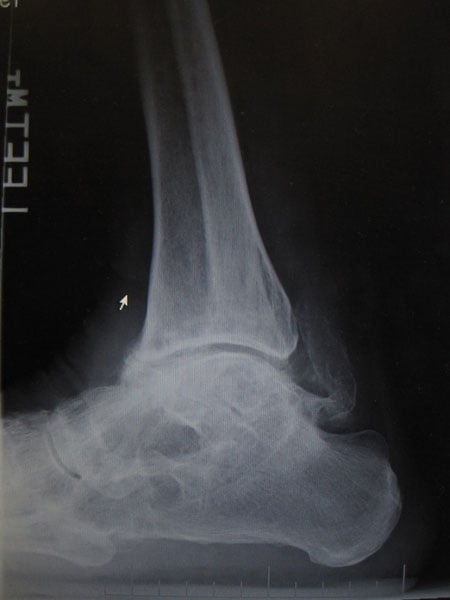

Case #74: Femur lengthening and deformity correction.